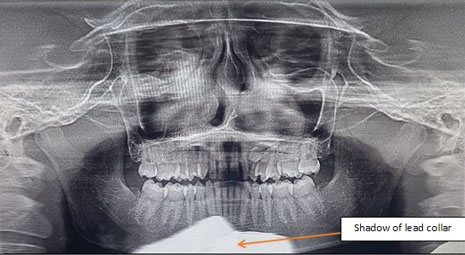

Panoramic radiograph revealed a well-defined unilocular expansile non-homogenous radiolucent lesion with smooth corticated borders, extending in the left maxillary sinus and left side of the nasal cavity. Internally, the pathology was associated with the radicular portion of the impacted canine of the second quadrant. The coronal portion of the impacted maxillary canine was noted distal to the radicular portion of maxillary lateral incisor, and the radicular portion in proximity to the roots of the maxillary premolars suggesting horizontal impaction. Superior displacement in floor of left maxillary sinus was noted, thereby causing reduction in sinus dimensions. Left lateral wall of the nasal cavity was not traceable. Over-retained deciduous maxillary left canine was present with evidence of external root resorption. Since the pathology was associated with impacted tooth/maxillary canine, an obvious diagnosis of adenomatoid odontogenic tumor (AOT) was considered. The inferior most part of the radiograph showed a diffuse well-defined radiopaque shadow in midline suggestive of shadow of thyroid/lead collar (Figure 2).

Figure 2: Panoramic radiograph, well-defined unilocular expansile non-homogenous radiolucency with well-defined corticated border noted in maxillary anterior region on the left side.